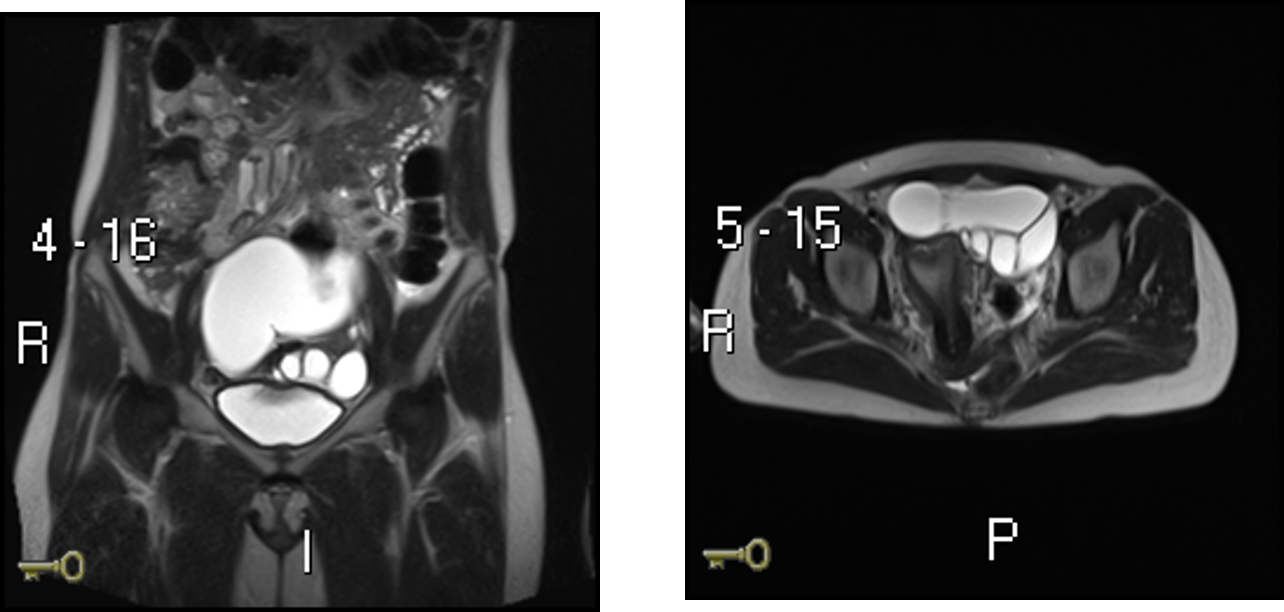

What abnormality is shown in this MRI ?

Hydrosalpinx - a distally blocked fallopian tube filled with serous or clear fluid. The blocked tube may become substantially distended giving the tube a characteristic sausage-like or retort-like shape.